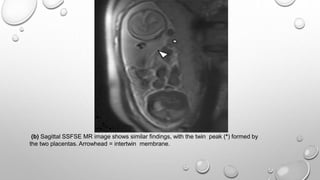

(b) Sagittal SSFSE MR image shows similar findings, with the twin peak (*) formed by

the two placentas. Arrowhead = intertwin membrane.

(b) Sagittal SSFSEMR image shows similar findings, with the twin peak (*) formed by the two placentas. Arrowhead = intertwin membrane.